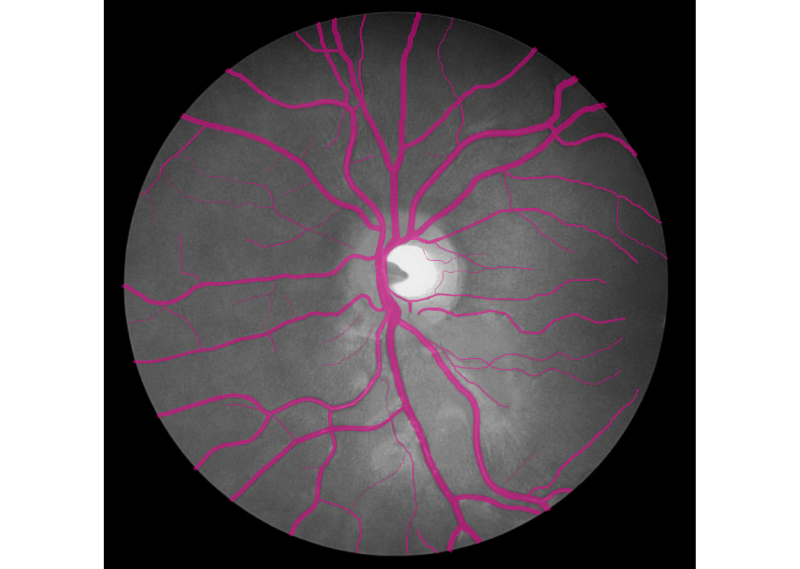

Hello world! In December of 1895, Wilhelm Röntgen the bones of his wife’s hand in the first X-ray photograph. “I have seen my death,” she said. This breakthrough had an incredible influence on 20th-century medical treatment. And latest Deep Learning advances open up new possibilities in this field. revealed Deep Learning has found great success in computer vision and other areas. And now it is actively transforming the world of medicine. AI helps doctors make more accurate diagnoses faster. Today we would like to share our thoughts and investigations into very promising direction: Human in the loop AI for medical image analysis within a single environment — . Supervisely Our platform allows to manage and annotate data, train NNs, apply them for automatic pre-annotation and then deploy them as API. Challenges with medical images IBM researchers that medical images, as the largest and fastest-growing data source in the healthcare industry, account for at least 90 percent of all medical data. estimate Challenge 1: data privacy Medical data is still personal and not easy to access. And due to data privacy concerns most of the public health centers are reluctant to share the data. Challenge 2: size of annotated data Annotation process is hard to outsource and only expert physicians can analyze medical images. This limitation leads to high costs and to the lack of annotated data. Challenge 3: quality of annotation tools Annotation tools, that can be used to extract insights from medical images, are still limited, in most cases publicly unavailable and requiring most analysis to be done manually. Challenge 4 (consequence of 1 and 2): segmentation challenge Datasets for segmentation task are typically extremely small compared to large public datasets of common images (COCO, PascalVoc and so on). Due to the size of datasets it is difficult to train very deep neural network architectures. Objects of interest can vary in size, shape and position. In combination with the “soft” boundaries it produces additional problems. Our goals We are going to overcome Challenge 3 and Challenge 4: give the industry end-to-end solution that makes human experts more efficient and automates routine tasks with powerful AI technologies. Supervisely: user interfaces We realize, that there is still a lot of work ahead: increase the number of convenient annotation tools and add the support of DICOM format, three dimensional images, sequences of images and so on. But these are only technical issues, first steps are already done and promising results are obtained. We are passioned to accelerate medicine and happy to be a part of global research community that drives deep learning revolution to healthcare. There could be no more important application of this new capability [deep learning] than improving patient care — Jensen Huang, NVIDIA CEO and co-founder Case-study: blood vessel segmentation in retina images There are a lot of Deep Learning medical applications in imaging: tumor detection, tracking tumor development, blood flow quantification and visualization, dental radiology and much more. Because we are not doctors, we looked for data we understand more or less. That’s why we decided to make research on blood vessel segmentation. Let’s take a look to one of the most popular public datasets in this field: (STructured Analysis of the Retina). STARE Dataset contains 28 annotated images with resolution 999 × 960. We consider the case that we have only . Other images will be used for final evaluation of quality. All training images are below: 6 annotated images in training dataset Here is the whole training dataset we use. This scenario is pretty close to real world: medical doctor annotates few images, then neural network is trained on this data and applied to other images for pre-segmentation. Then doctor just corrects the NN predictions. Such approach is called Human in the loop AI. It is aimed to significantly accelerate efficiency of human expert. PS. Thanks to Supervisely entire research took 2 hours without haste ☕. Step1: training data augmentation We had only 6 annotated images. To train NN we have to automatically increase the size of dataset. Supervisely has special module to perform augmentations: DTL (Data Transformation Language). It allows to configure entire augmentation process in a simple json-based format and perform it in a few clicks. How DTL query interface looks like In this use case we did horizontal/vertical flips and relatively big random crops. We got 264 training examples from only 6 annotated images. Here is the visualization of computational graph that we applied to our data: Resulted crops after augmentation Step2: train neural network There are few state of the art Neural Networks for semantic segmentation in Supervisely. One of them — our custom UNet-like architecture. It was chosen because: we have small training dataset, it is accurate and fast to train. Also we use combination of Binary Cross Entropy and Dice losses because of class imbalance problem. Vessels pixels covers only few percents of image area in contrast to background pixels. We trained NN 50 epochs. It is interesting to visualize Neural Network predictions during training. We take unseen image and apply NN after each epoch. Here you can see how our NN becomes smarter over time. Supervisely supports multi GPU training. Each epoch takes around 20 seconds on four GPU. Total training time — around 17 minutes. Step3: automatic pre-segmentation We applied NN to new images. Let’s compare predictions with ground truth. : NN predictions, : ground truth Left Right As you can see from this comparison every relatively bold vessels are segmented. There is no noise. It means that the human only have to draw few hairlines with “polyline” tool. Also, as we understand real data has much bigger resolution that public data we use in this experiment. We think that this fact is crucial for the quality of hairlines segmentation. Resolution of publicly available images is not enough. Look at this example: do you see the vessels that are annotated by doctors? Left: meme, Middle: original image, Right: doctor’s annotation Step4: manual correction As you can see from images above the quality of automatic pre-annotation is pretty good. It is much more easier and faster to correct NN predictions than annotate from scratch manually. We were not lazy and made time measurements: how much time we need for manual annotation from scratch vs correction of NN predictions. Manual annotation from scratch: . Correction of NN predictions: . 36 minutes / image 4 minutes / image Conclusion is obvious. Final thoughts Deep Learning has a huge potential in medical image analysis. AI is changing the way doctors diagnose illnesses. Main important difference between doctor and deep learning algorithm is that doctor has to sleep. Neural Network can process millions of images and can be continuously improved. Human in the loop approach and automatic segmentation with Supervisely will let us create large datasets faster. All steps are done without coding. It means that user with no ML background have access to state of the art AI. So ML community will build more services to help doctors provide better and quicker treatment. Let’s make the future together. If you found this article interesting, then let’s help others too. More people will see it if you give it some 👏.